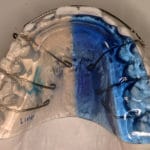

Pour les enfants et les jeunes plutôt des appareils amovibles, ainsi que des appareils fixes collés (pièces métalliques) pour aligner les dents. Ceux-ci peuvent être choisis en option transparentes.